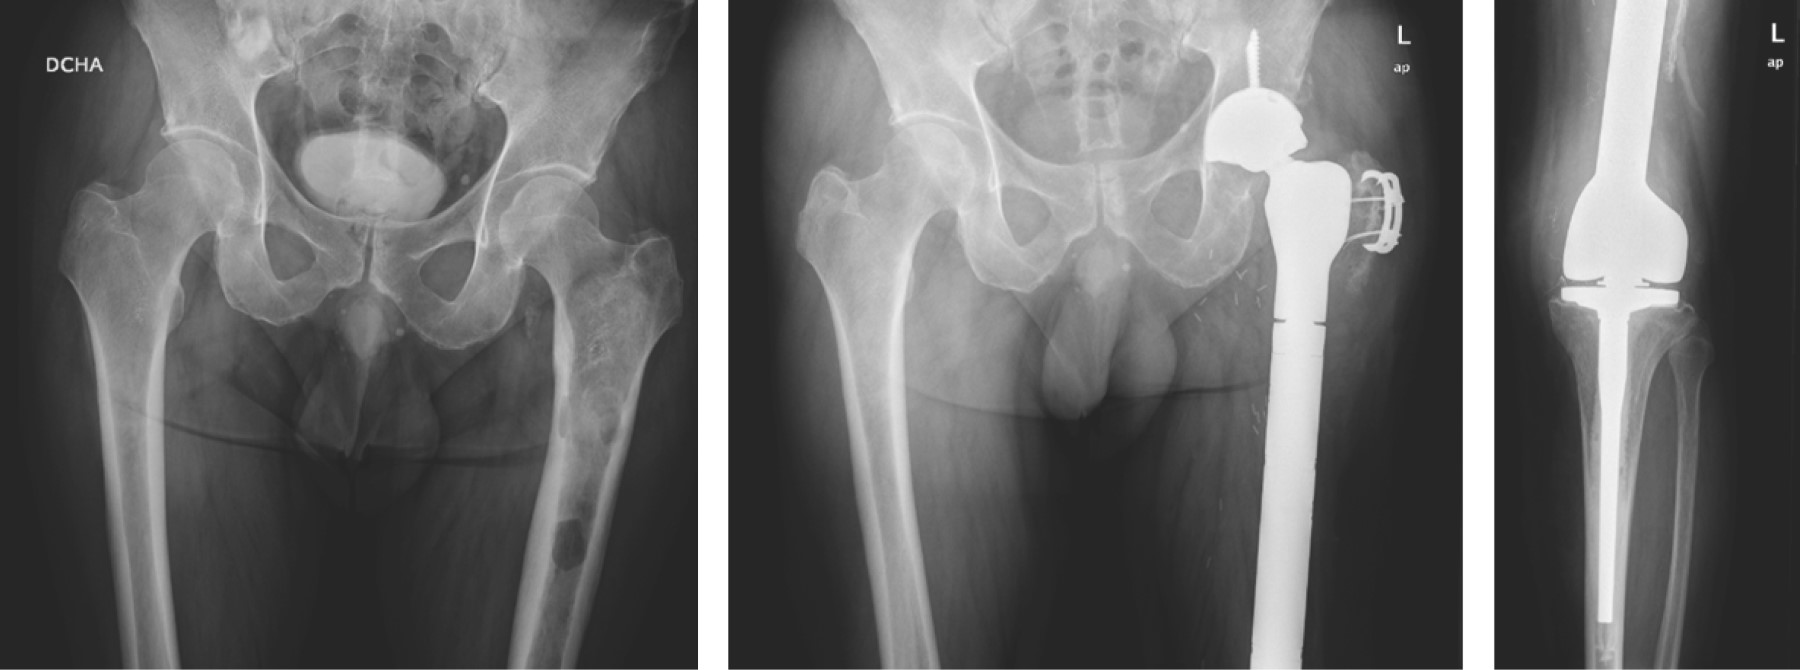

La reconstrucción tras la resección tumoral en los tumores pélvicos (nueve pacientes) se llevó a cabo mediante prótesis de anclaje ilíaco tipo "cucurucho de helado" (Coned®; Stanmore Worldwide Ltd, Elstree, UK) en siete casos y en los dos pacientes restantes se utilizaron prótesis pélvicas a medida con vástagos femorales modulares (Figura 2). En el resto de las localizaciones se utilizaron en todas ellas megaprótesis modulares: megaprótesis de fémur proximal con artroplastía de cadera en 11 casos, de fémur distal con artroplastía de rodilla en tres casos de tumoraciones femorales y dos de tibia proximal y megaprótesis de fémur total en tres pacientes (Figura 3). Con respecto a la fijación, ocho megaprótesis fueron no cementadas (26.7%), mientras que el resto presentaban alguno de los componentes cementados (73.3%). En ocho de los pacientes con resección del fémur proximal se conservó el trocánter mayor mediante reanclaje al vástago femoral para conservar la acción de los rotadores de cadera y en dos pacientes intervenidos mediante megaprótesis de fémur total se mantuvo la porción distal del fémur para mantener la musculatura aductora (Figura 4).

Figura 2

Figura 3

Figura 4